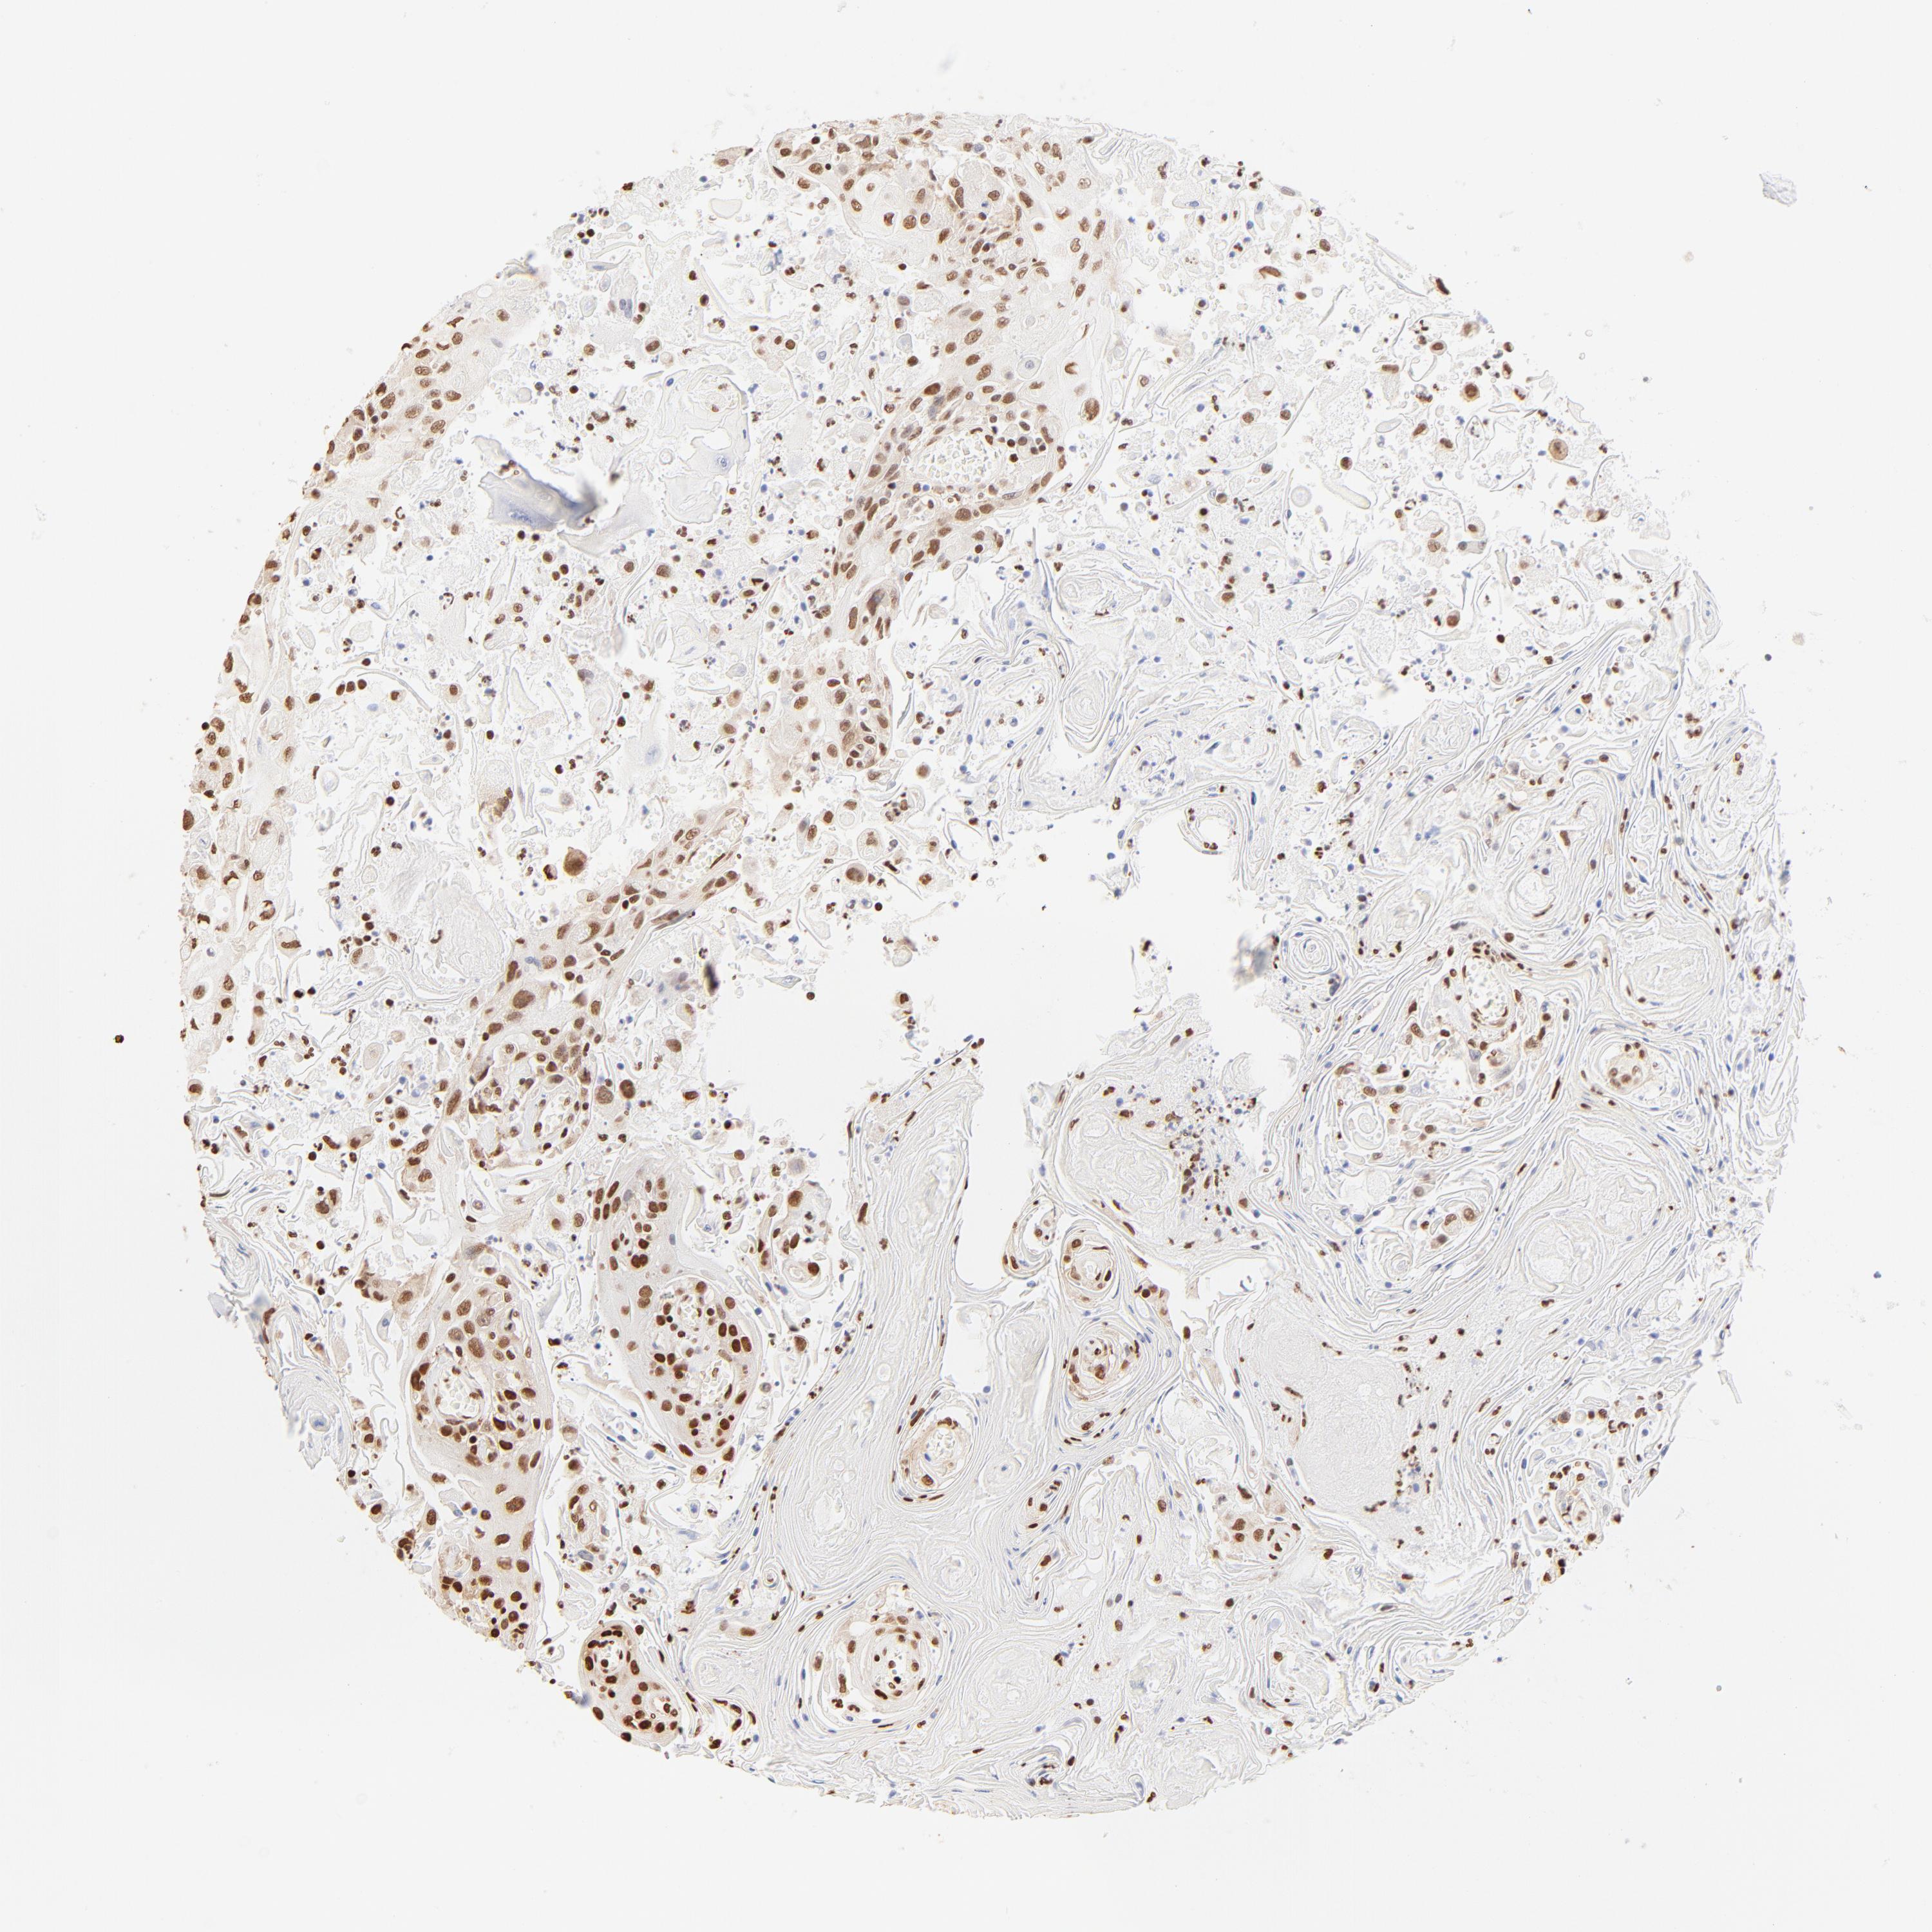

HEAD AND NECK CANCER - Protein expressioni

A mouse-over function shows sample information and annotation data. Click on an image to view it in a full screen mode. Samples can be filtered based on level of antibody staining by selecting one or several of the following categories: high, medium, low and not detected. The assay and annotation is described here.

Antibody stainingi

Antibody staining in the annotated cell types in the current human tissue is reported as not detected, low, medium, or high, based on conventional immunohistochemistry profiling in selected tissues. This score is based on the combination of the staining intensity and fraction of stained cells.

Each image is clickable and will lead to virtual microscopy that enables deeper exploration of all samples and also displays staining intensity scores, fraction scores and subcellular localization as well as patient and tissue information for each sample.

Antibody HPA003444

Staining

High

Medium

Low

Not detected

Intensity

Strong

Moderate

Weak

Negative

Quantity

>75%

75%-25%

<25%

None

Location

Nuclear

Cytoplasmic/membranous

Cytoplasmic/membranous,nuclear

Squamous cell carcinoma, NOS

Neoplasm, malignant, NOS

Adenocarcinoma, NOS